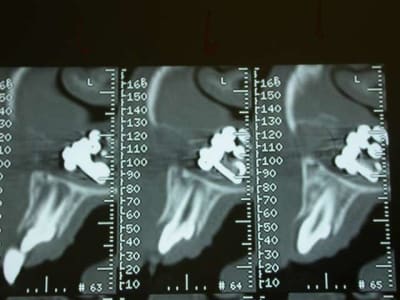

l'objet: une petite chainette boule métallique (celles qui sont accrochées à certains vetements et qu'on retrouve sur les bouchons de baignoire) complétement oxydée (noir de chez noir, avec diminution du diametre de certaines boules) .

temps de séjour estimé dans les fn: 4-5 ans

Une fois le scanner réalisé, je vois bien qu’il s’agit d’un objet composé de boules et l’adresse illico à son orl. Il la reçoit dans la foulée, et au vu du scanner, se refuse d’intervenir de peur de renvoyer plus loin l’objet. A son tour, il l’adresse à un hopital spécialisé enfants (Robert Debré). Au service ORL, ils tentent de retirer l’objet avec une pince (comme Dr House le faisait dans un épisode) et rien de neuf, aucune progression.

L’ORL qui s’occupe de Zoe est têtu et tente un dernier coup, en branchant une aspiration chirurgicale hyperpuissante et en couplant l’action de celle-ci avec la pince de House. Et petit à petit, il arrive à sortir cette fameuse chainette. Le tout sans anesthésie.